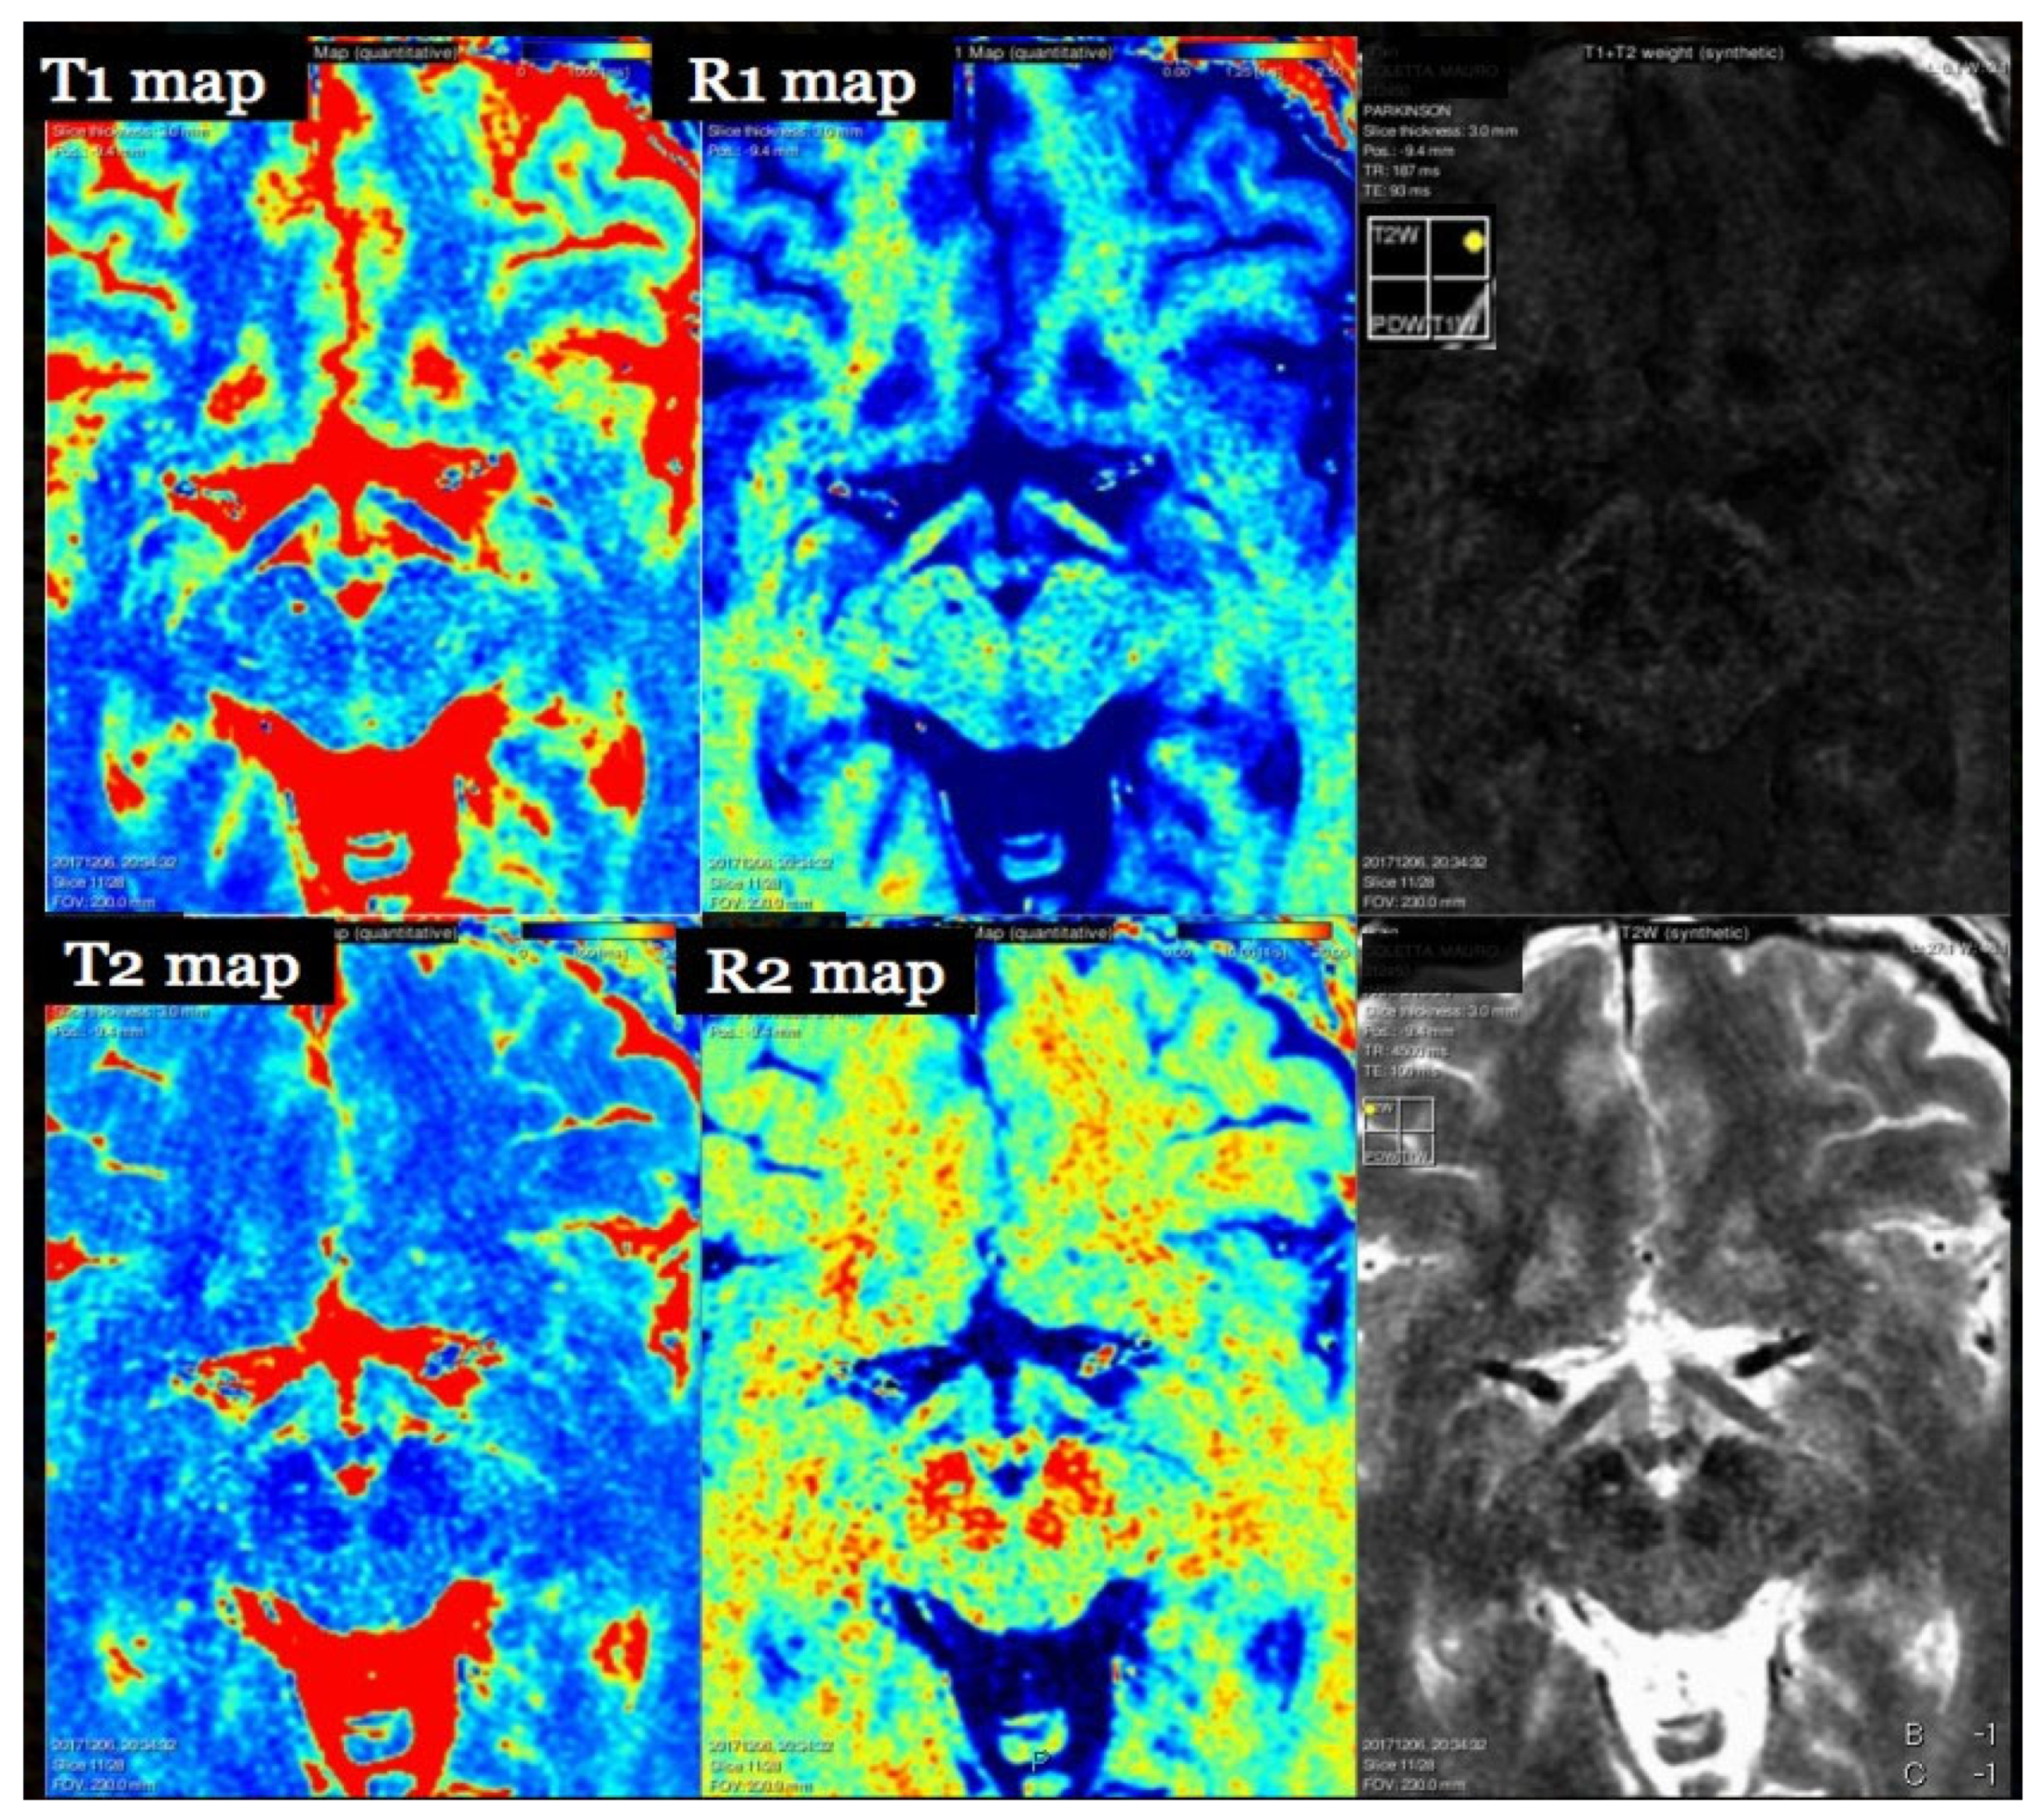

7. T1 Relaxometry

- Hagiwara, A.; Warntjes, M.; Hori, M.; Andica, C.; Nakazawa, M.; Kumamaru, K.K.; Abe, O.; Aoki, S. SyMRI of the Brain. Investig. Radiol. 2017, 52, 647–657. [Google Scholar] [CrossRef]